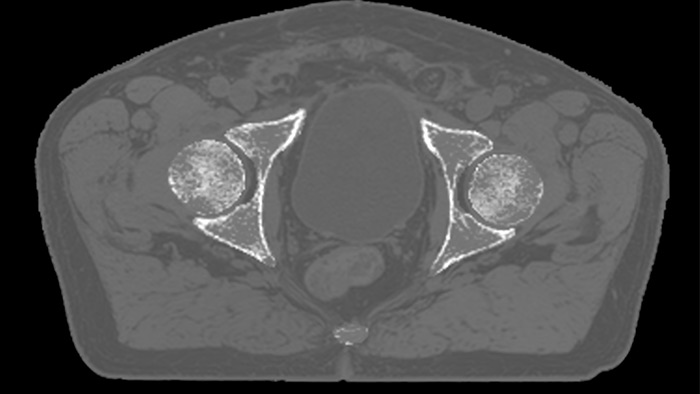

MRCAT Pelvis